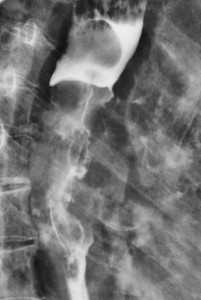

Метастазы в легких — фото рентгенограммы. Округлые тени — метастазы рака пищевода. Хорошо виден большой узел округлой формы вблизи переднего отрезка 2-го ребра. На снимке справа - циркулярное сужение пищевода за счет опухолевого утолщения его слизистой оболочки.

![image005]()

![image007]()

Как выглядят метастазы в легких на рентгене? Слева — узловые образования у пациента с раком яичка. Справа - метастазы рака яичников гематогенного характера с выраженным опухолевым лимфангиитом (обратите внимание на деформированный сетчатый, линейный характер легочного рисунка).